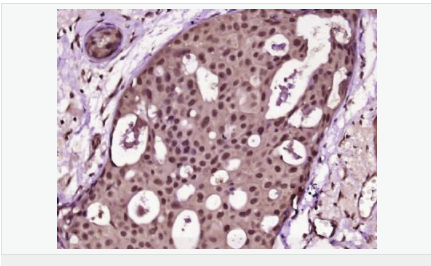

Ki67 antigen is the prototypic cell cycle related nuclear protein, expressed by proliferating cells in all phases of the active cell cycle (G1, S, G2 and M phase). It is absent in resting (G0) cells. Ki67 antibodies are useful in establishing the cell growing fraction in neoplasms (immunohistochemically quantified by determining the number of Ki67 positive cells among the total number of resting cells = Ki67 index). In neoplastic tissues the prognostic value is comparable to the tritiated thymidine labelling index. The correlation between low Ki67 index and histologically low grade tumours is strong. Ki67 is routinely used as a neuronal marker of cell cycling and proliferation.

細胞增殖標志物(Proliferation Marker)

Ki67與PCNA一樣,為細胞增殖的一種標記,在細胞凋亡中S、G2 、M期均有表達,G0期缺如。

Ki-67增殖指數(shù)高低與許多腫瘤的分化程度、浸潤、轉(zhuǎn)移以及預后密切相關(guān),因此被廣泛作為各種惡性腫瘤的必檢項目之一。